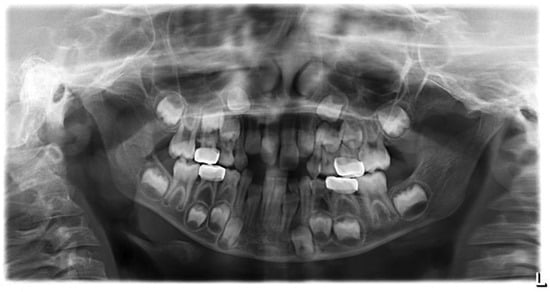

After a three-month period, we performed a panoramic radiograph (Figure 4), and every six months, clinical and radiograph exams were collected. At the end of four years of follow-up, clinical evaluation revealed a good marginal adaptation and gingival health (Figure 5), and radiographic exam showed normal occlusion in all the first permanent molars (Figure 6). Moreover, at each appointment, information was given regarding gingival health, occlusal contacts, adaptation of crown margins, and the presence of clinical signs of infection. No additional treatment was needed during the follow-up period.

Figure 4. Panoramic X-ray of three-month follow-up.